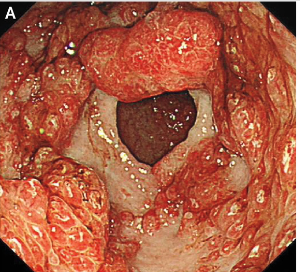

A few of the images from Figure 2:

- Polyposis: Multiple [hamartomotous] polyps are found in the stomach and colon. These polyps can vary in size and number.